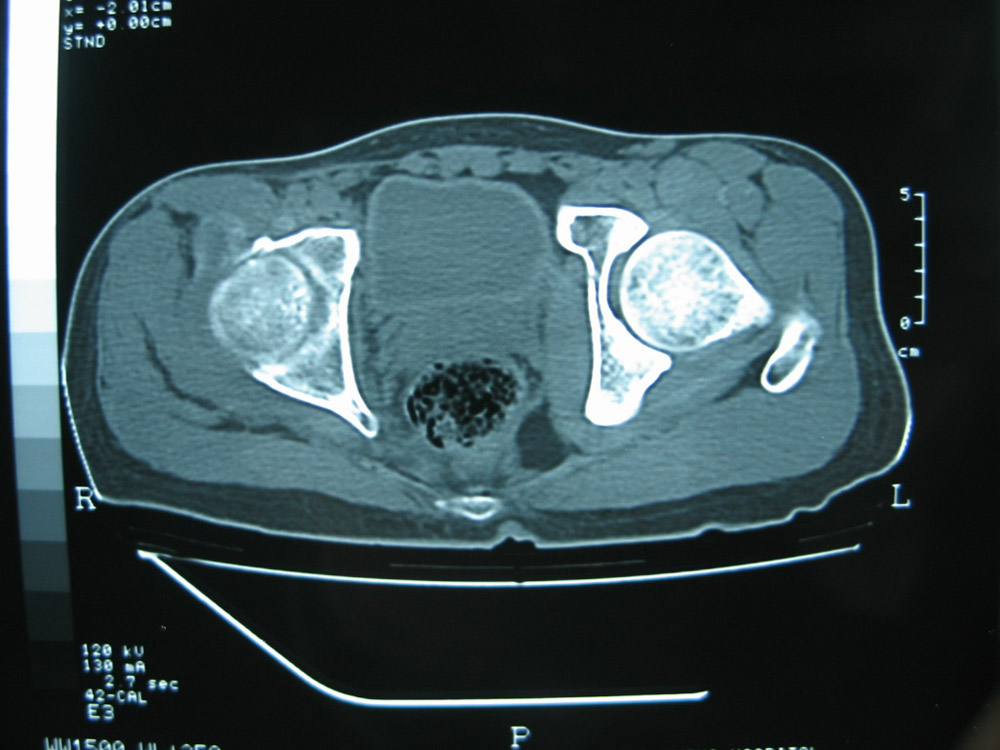

以下是引用卜一在2007-1-25 16:33:00的发言:[br]右侧髋关节股骨头及髋臼骨骨小梁疏松 粗糟,股骨头外形毛糟,软组织似肿胀,间隙略变窄.考虑:1 髋关节结核可能性大.2 缺血性坏死?3 化脓性髋关节炎?

以下是引用hhcckk在2007-1-25 17:18:00的发言:[br][br]支持髋关节结核,[br]依据关节面破坏,有脓肿,脓腔内有钙化,关节周围增生不明显,鉴别[br]1化脓性的病变增生明显,临床上有高热[br]2创伤引起的关节炎,无菌坏死不会引起关节面的破坏,而且不会在这么短的时间内出现[br]